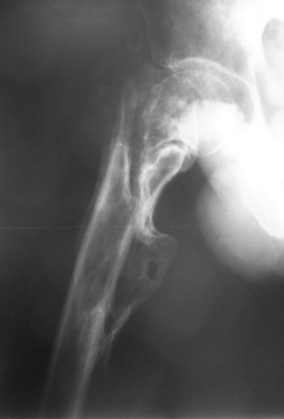

Уважаемый Глеб! Укорочение наверное побольше, да и наружно-ротационная установка скорее всего присутствует. Суставная щель прекрасная, головка живее всех живых. Ратую за подвертельную с латерализацией: исключает нарушение механической оси («исключает вальгус в коленe»), максимально удлиняет без натяжения m.iliacus. Для иллюстрации остеотомия-переделка (слава богу не автопеределка) у мужчины 65 лет.

Филипчук.

PS. Извините за качество последнего снимка, рентгенограмма выполнена по м. жительства, там где был проведен синтез. Последний снимок выполнен через 2 мес. п\о, больной без разрешения начал наступать, слава богу все обошлось.